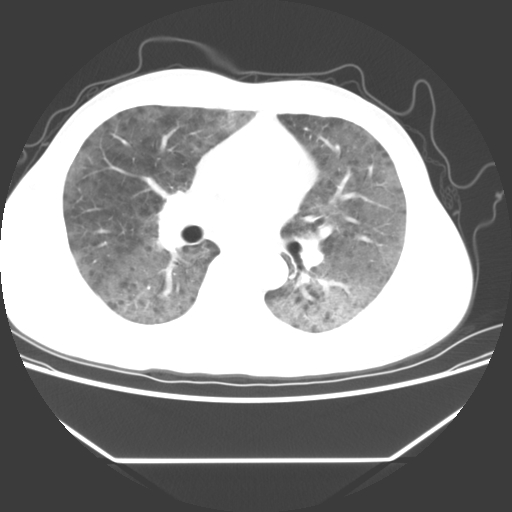

病人55岁,咳嗽,胸闷

忘了传病史了,病人55岁,咳嗽,胸闷

两肺部呈“毛玻璃”状改变,原因待查考虑感染性病变

病人是否发烧,两肺“磨玻璃”影,其间见空气支气管征和碎路石征。考虑肺泡蛋白沉着症。

两肺广泛对称磨玻璃样影,密度不均,考虑机遇性肺部感染。

双肺弥漫磨玻璃样病变,病史很重要。有感冒或发烧史,甲流不除外。无发烧可考虑肺泡蛋白沉积,但肺泡蛋白沉积边缘往往较清晰,与正常肺组织分界清晰

两肺弥漫间质性病变,考虑肺泡蛋白沉着症。建议进一步检查。

两肺“磨玻璃”影,其间见空气支气管征和碎路石征。考虑肺泡蛋白沉着症。